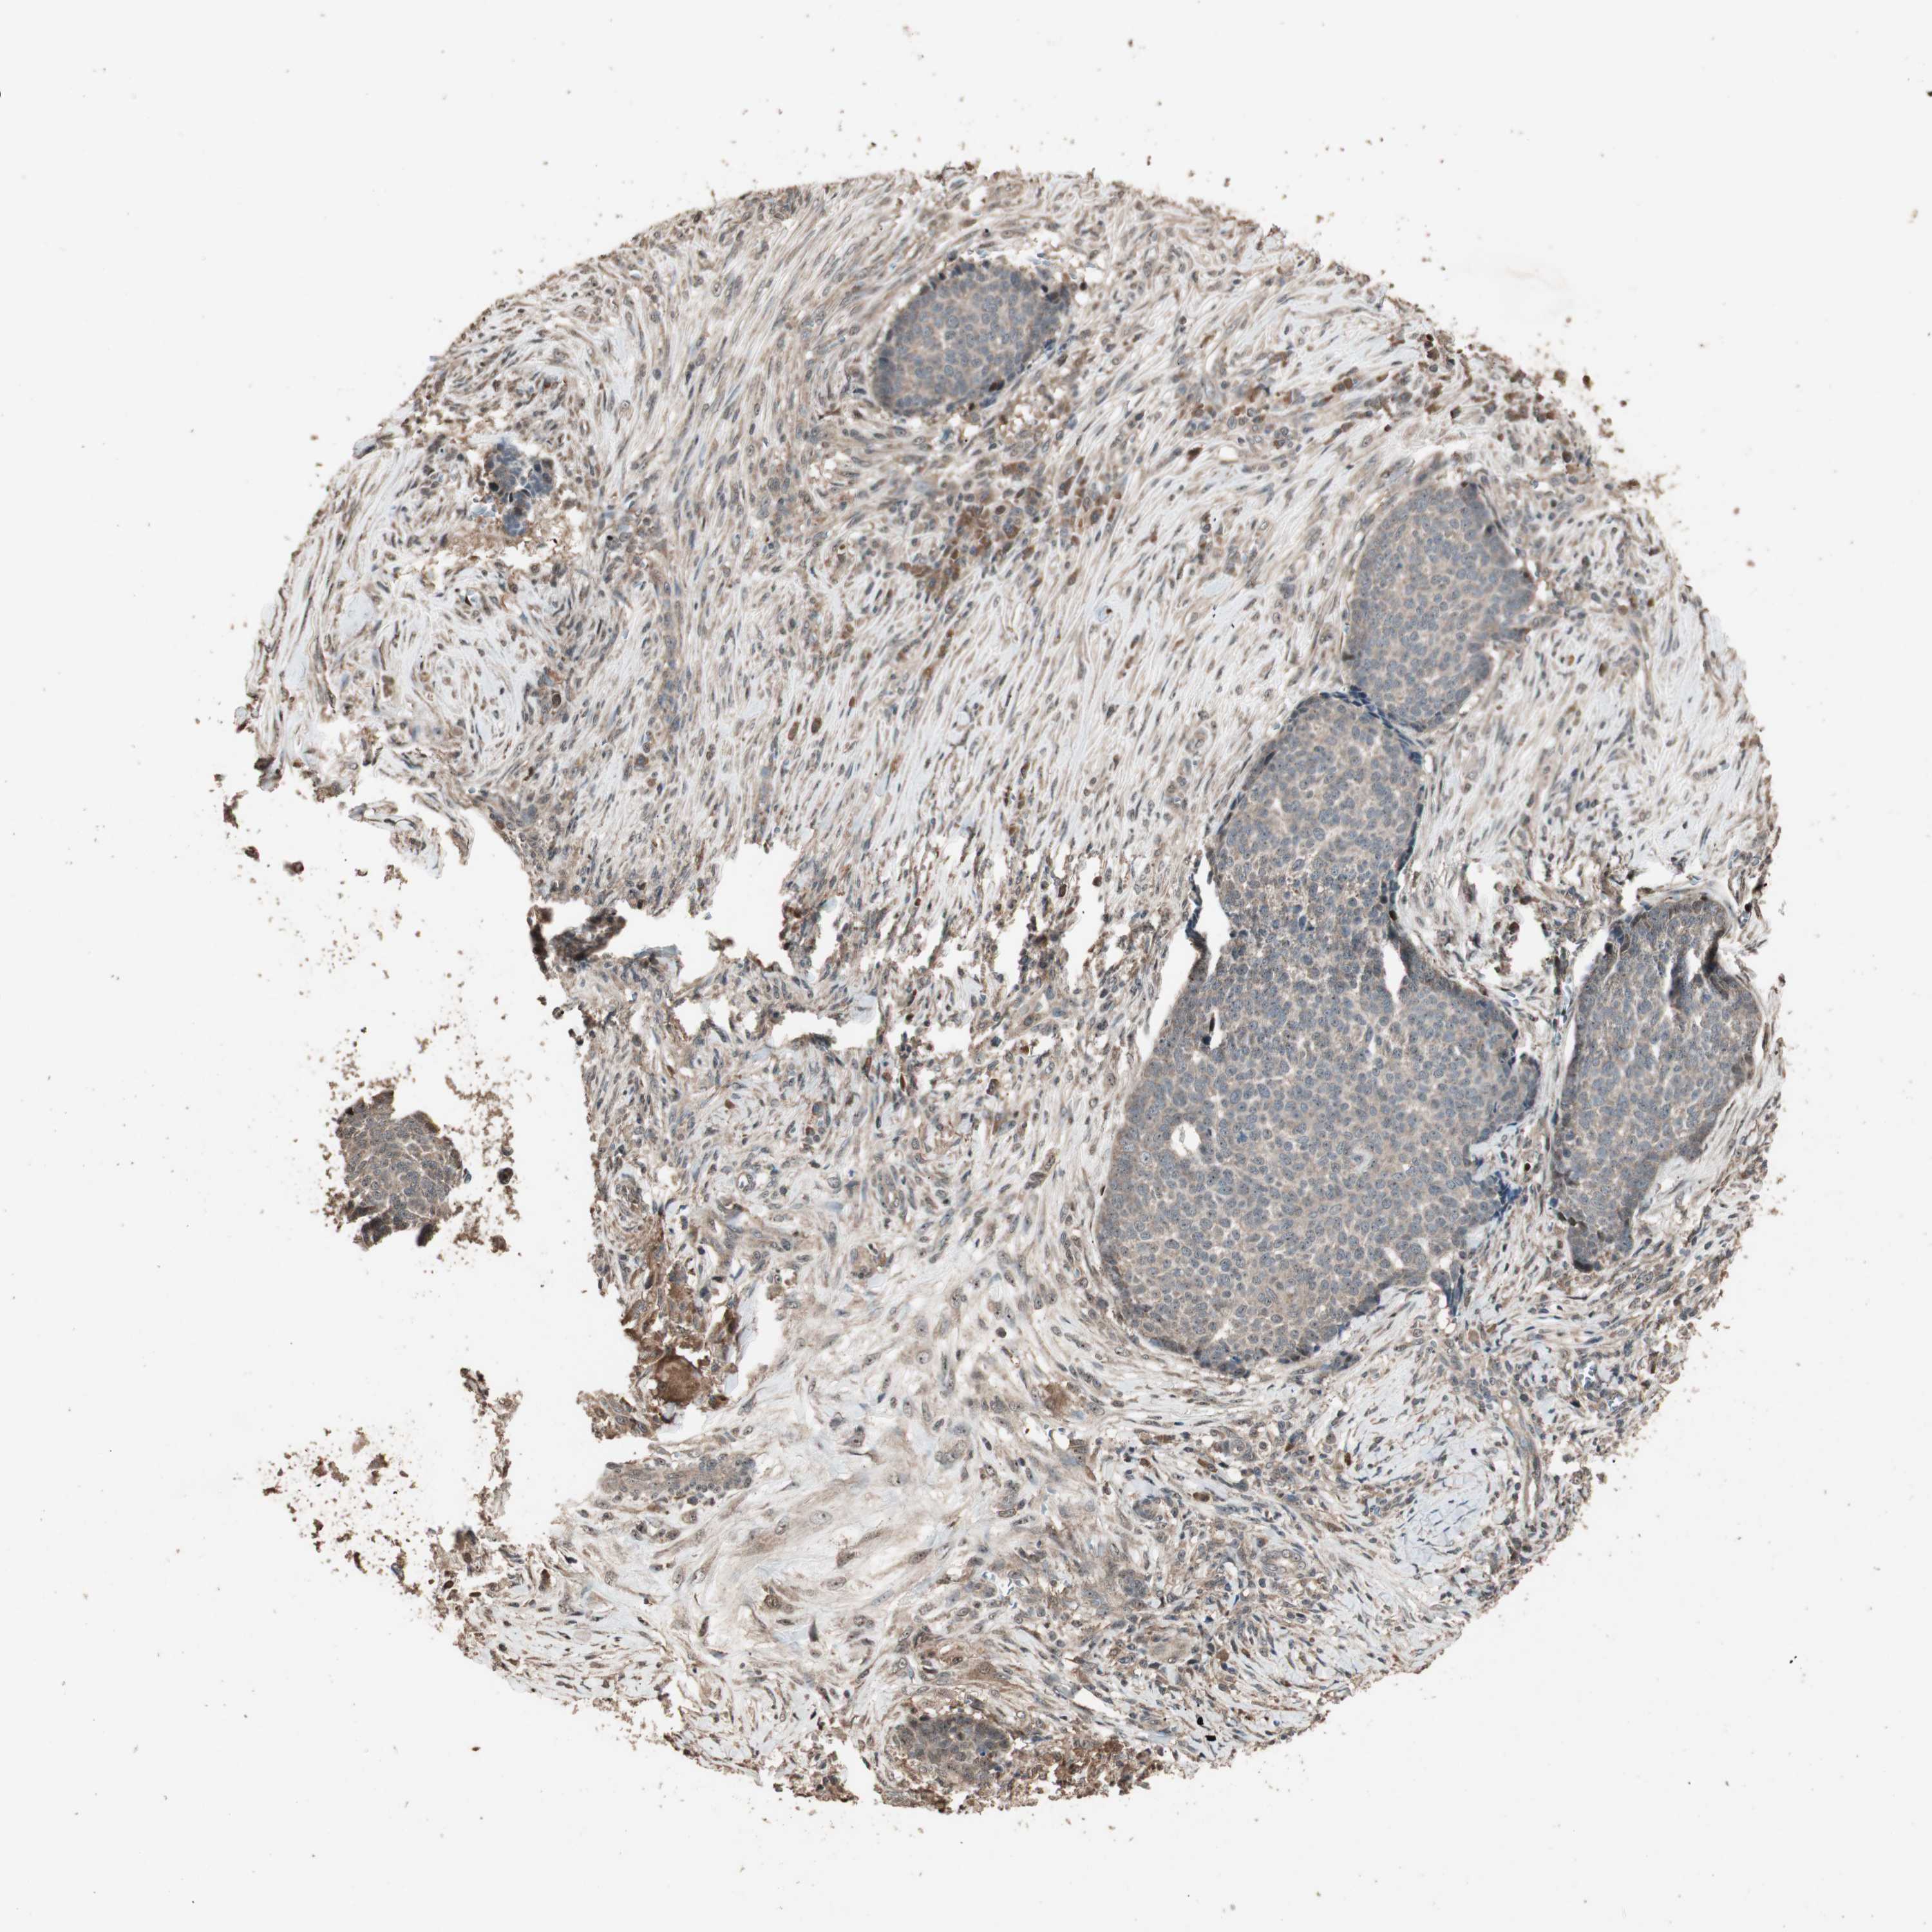

Basal cell and squamous cell cancer

SKIN CANCER - Protein expressioni

A mouse-over function shows sample information and annotation data. Click on an image to view it in a full screen mode. Samples can be filtered based on level of antibody staining by selecting one or several of the following categories: high, medium, low and not detected. The assay and annotation is described here.

Each image is clickable and will lead to virtual microscopy that enables deeper exploration of all samples and also displays staining intensity scores, fraction scores and subcellular localization as well as patient and tissue information for each sample.

Antibody HPA006287

Staining

High

Medium

Low

Not detected

Intensity

Strong

Moderate

Weak

Negative

Quantity

>75%

75%-25%

<25%

None

Location

Nuclear

Cytoplasmic/membranous

Cytoplasmic/membranous,nuclear

Squamous cell carcinoma, NOS

Squamous cell carcinoma, metastatic, NOS

Basal cell carcinoma